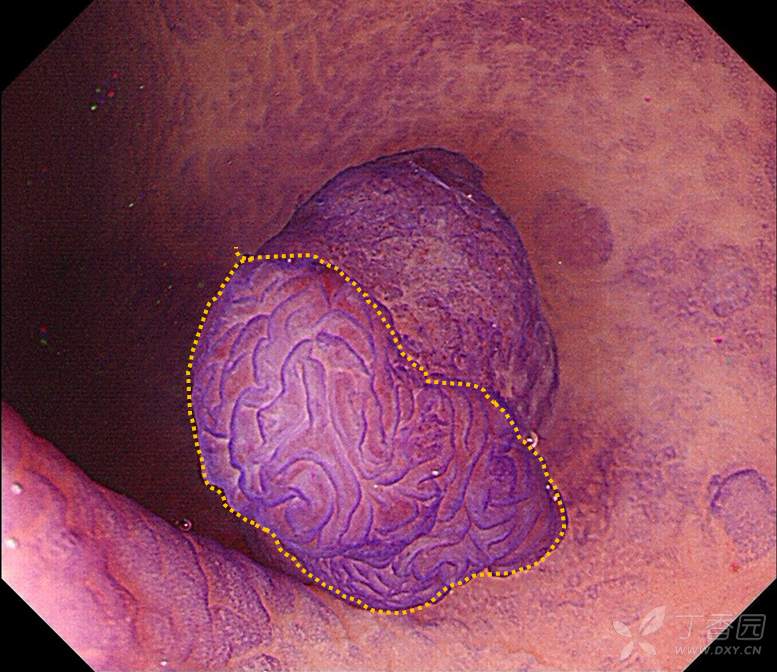

专注早癌诊断,从整体形态到微观表面,详细的判断:JNET、Pit pattern、浸润深度?

这是在跟老师发现的一例病人,在发现病人之后,通过不同的方法,比如NBI、放大、化学染色,对这个病变通过不同的角度,从宏观到微观细致的观察,详细的分析,以便于大家能够更好的理解:

一、pit pattern 分型的实际具体的形态是什么样子的?

二、JNET分型的特点和细微差别又是什么?

三、不同形态的病变,不同的分型的相应形态下对应的病理状态是什么?